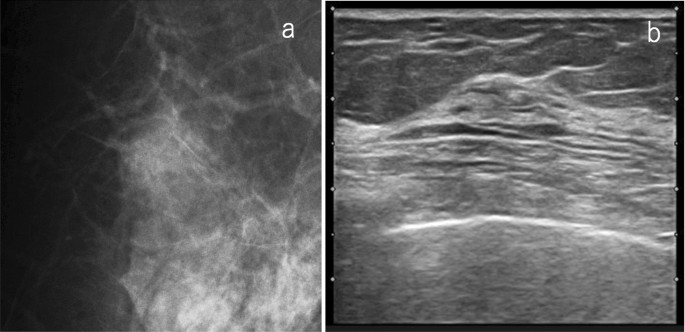

If mammography does not detect any malignancies (SMC1, 2), ultrasound is highly useful when the breast composition is heterogeneous or extremely dense. The ultrasound exam can detect occult cancers identified in mammography a priori, and can consequently increase sensitivity (Fig. 1). On the other hand, the fatty areas on the mammogram are not too much of a concern on ultrasound.

A case with no malignant findings on mammography. a Mammography: the breast composition is extremely dense, SMC 1. b Ultrasound: irregular, not parallel, hypoechoic mass, SUC 4. The overall assessment category: SC 4. Histopathology: invasive ductal carcinoma, grade 3 (SMC screening mammography category, SUC screening ultrasound category, SC screening category)